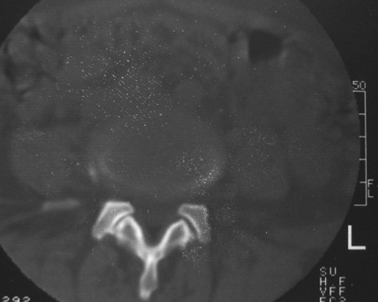

以下是引用dyqct在2007-3-1 18:04:00的发言:[br]腰5、骶1呈溶冰状骨质破坏,边界清楚,无明显硬化,内见多数沙粒状死骨,周围软组织肿胀。[br]考虑:腰5、骶1结核,建议严格抗结核治疗后复查。

以下是引用gaozhengyi在2007-3-1 19:39:00的发言:[br]骨质破坏并砂砾样死骨为椎体结核的表现。椎体结核骨质破坏区的特点是呈虫蚀状,常可见硬化缘。死骨表现为片状高密度影,正如本例。

以下是引用织梦在2007-3-1 21:17:00的发言:[br]腰5椎体骨质碎裂,密度增高,边缘较毛糙,椎体内可见一斜行透亮线及骨质硬化,周围软组织肿胀不明显。本人认为还应该再仔细询问病史,看是否有外伤史。这个病例我考虑腰5椎体陈旧性骨折继发感染可能。